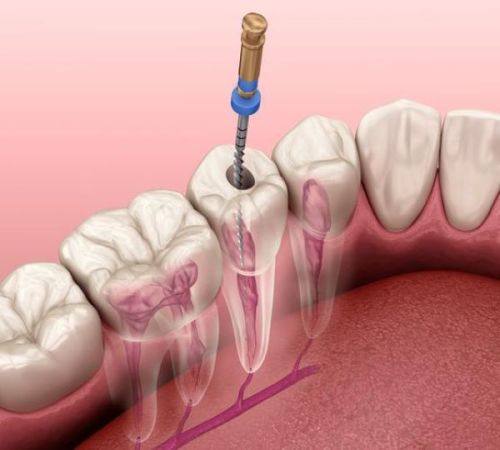

根管治疗:针对牙髓病变的规范诊疗服务

西吉县雅康口腔门诊部根管治疗:500元起